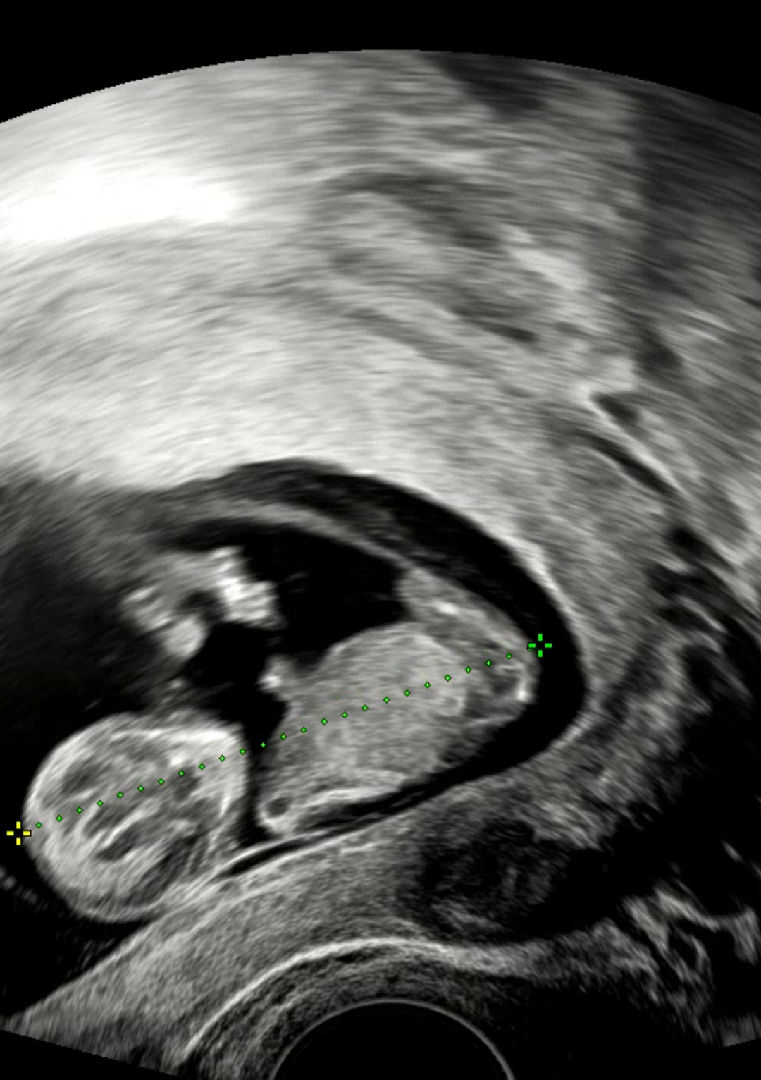

10주 5일 초음파

오늘 10주 5일차 초음파 검진하고 베동맘들 조언에 초코우유 먹고 검사하니 너무 잘 움직이는 아기 보았지 모예요ㅜㅜ🩷 2주 뒤에 1차 기형아 검사인데 너무 걱정되어서 오늘 초음파 사진 올려보아요. 아래의 사진으로 성별이랑 목투명대 정상인지 알 수 있을까요? 아직 10주차라 여러 변수는 있겠지만 고수 베동맘들조언 부탁드려요😭

10주면 의사도 성별 유추가 안될건데요....^^; 많이들 생각하시는 각도법도 12주부터 생식기 부분 잘나온 옆모습으로 보니까요 15~16주는 남아여아 모두 생식기가 튀어나와있어요 그래서 성별 반전이 심심찮게 발생되구요 궁금하신 마음 이해하지만 조금 더 기다려보셔야 할 것 같아요 그나저나 애기 옆모습 배 통통한게 넘 기엽네요 😏